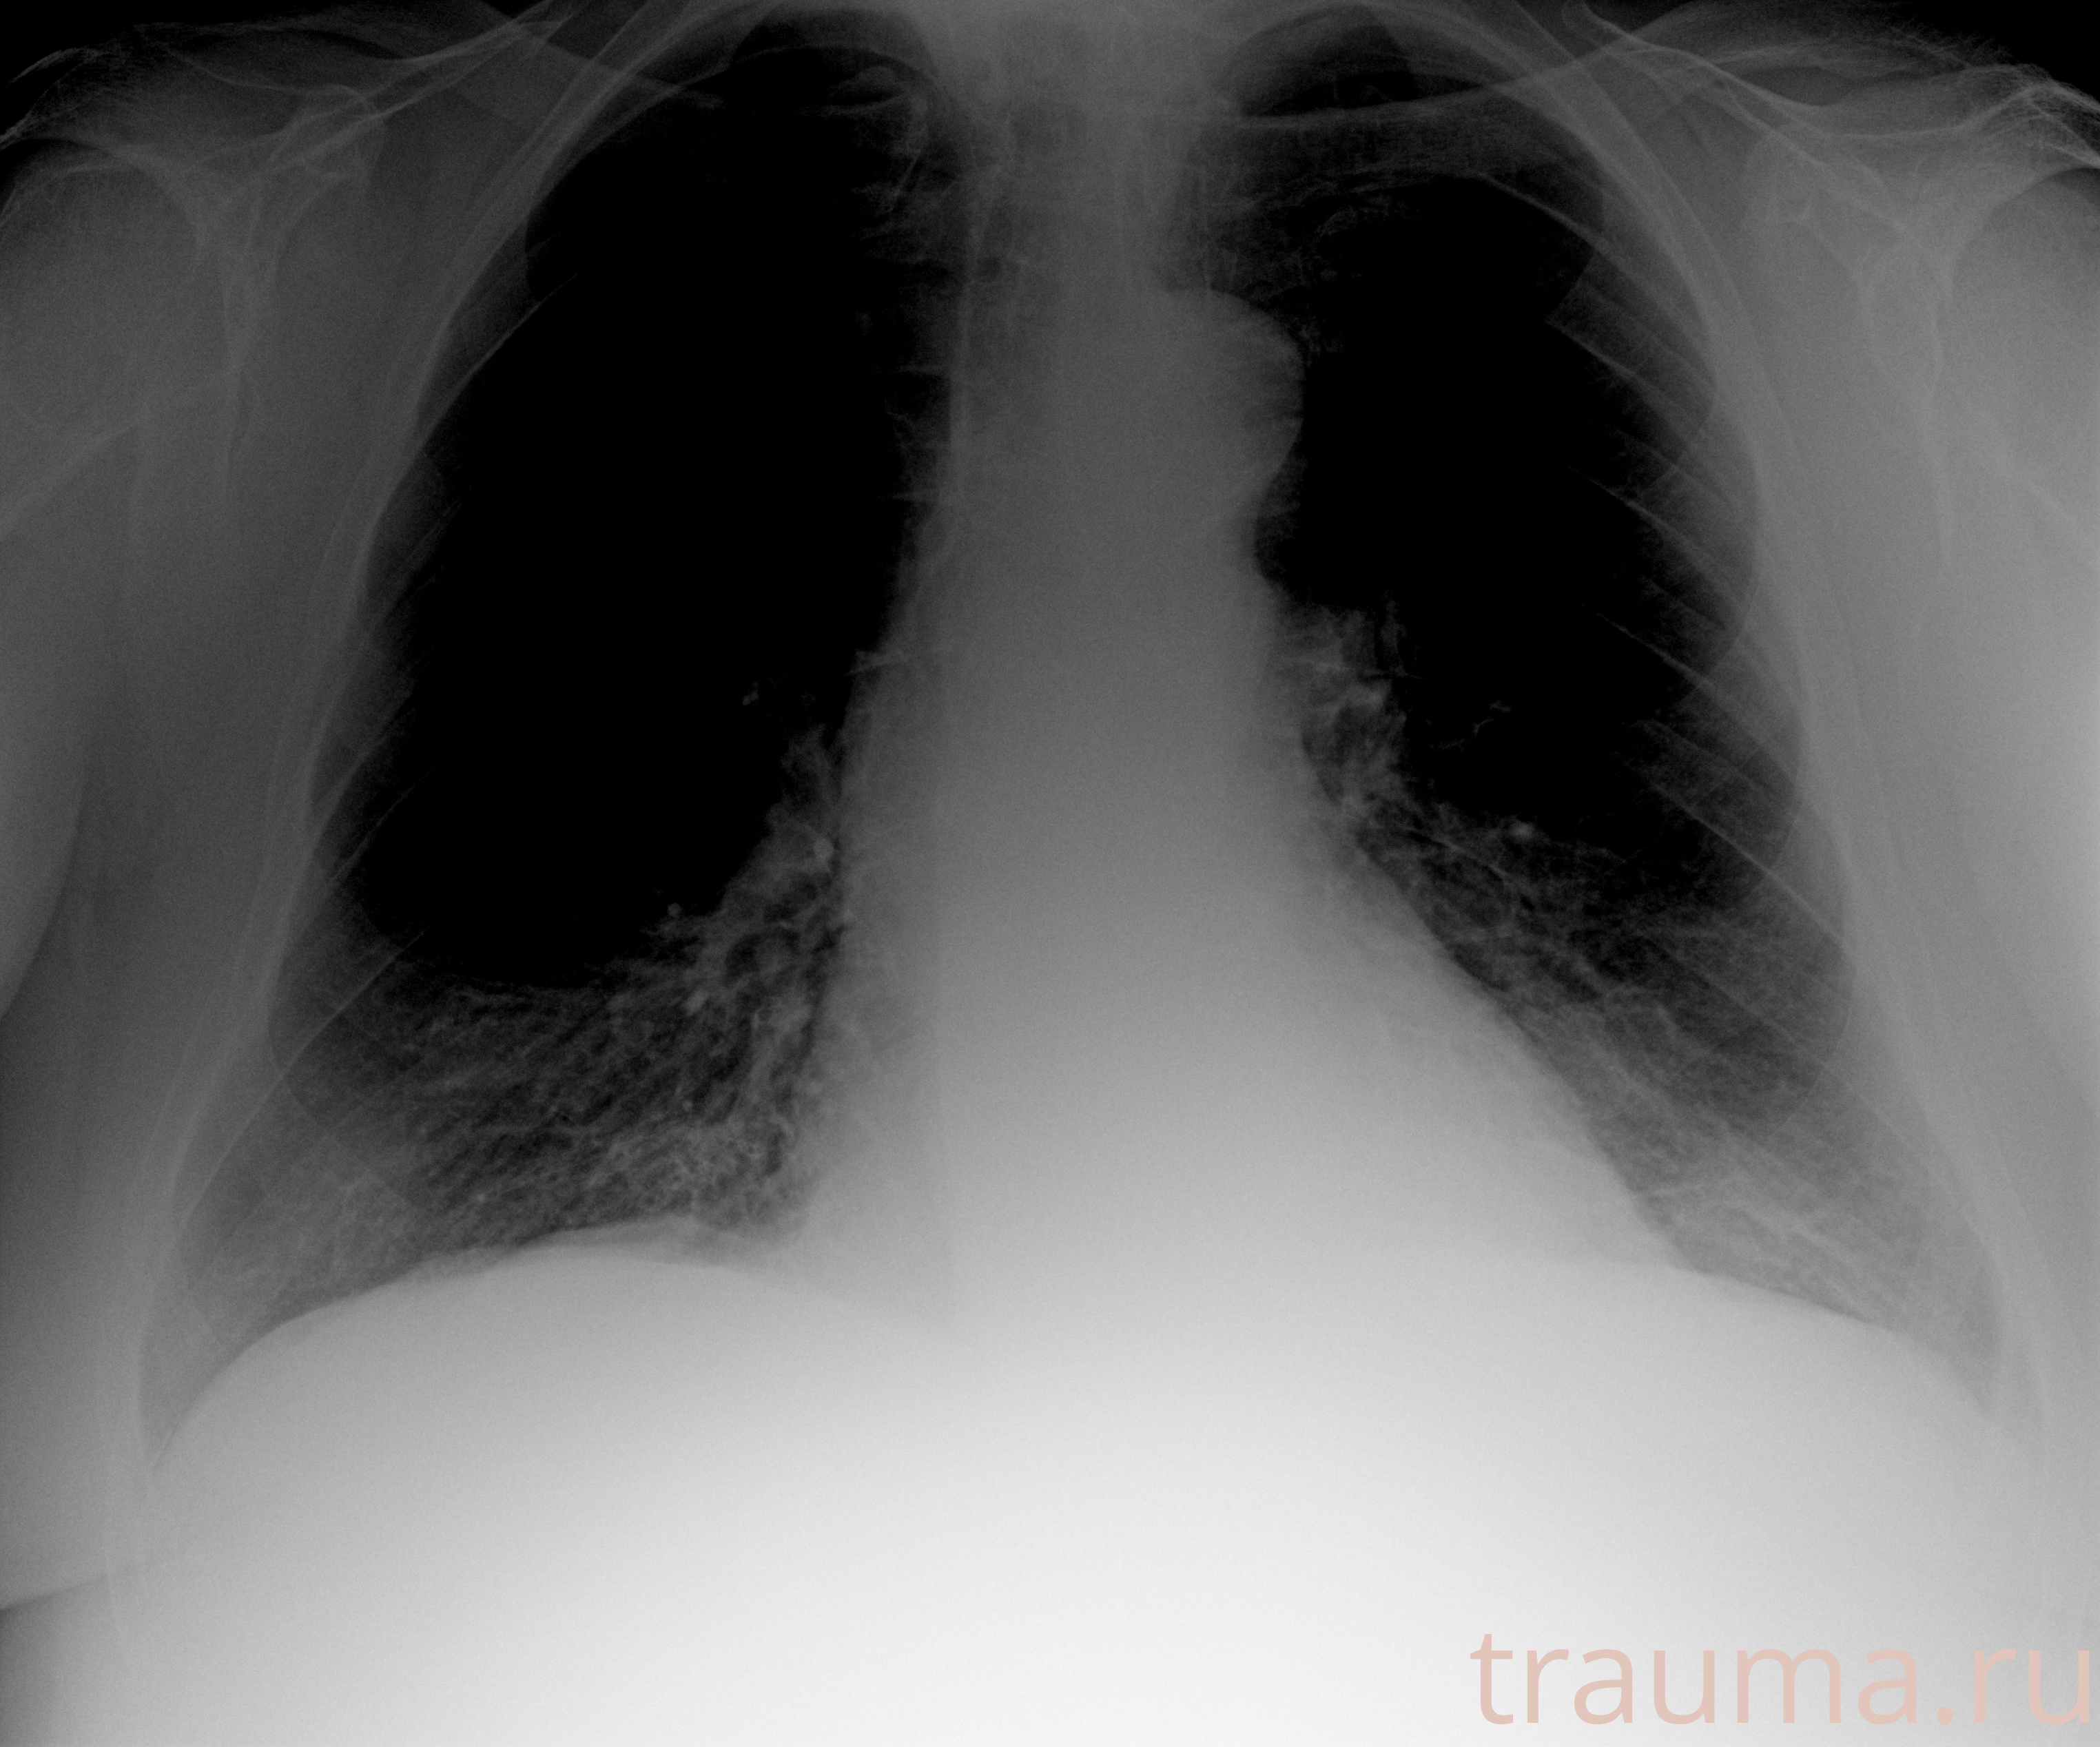

Рентгенограммы

Рентген на дому: по вашему адресу приезжает врач-рентгенолог, травматолог-ортопед с мобильным рентгеновским аппаратом, проводит диагностику травмы или заболевания, делает необходимые рентгенограммы, дает рекомендации по дальнейшему лечению. Получить качественные снимки в домашних условиях возможно благодаря уникальной методике, разработанной МосРентген Центром для института  Склифосовского

при переломе шейки бедра и пневмонии от компании МосРентген Центр - партнера Института имени Склифосовского